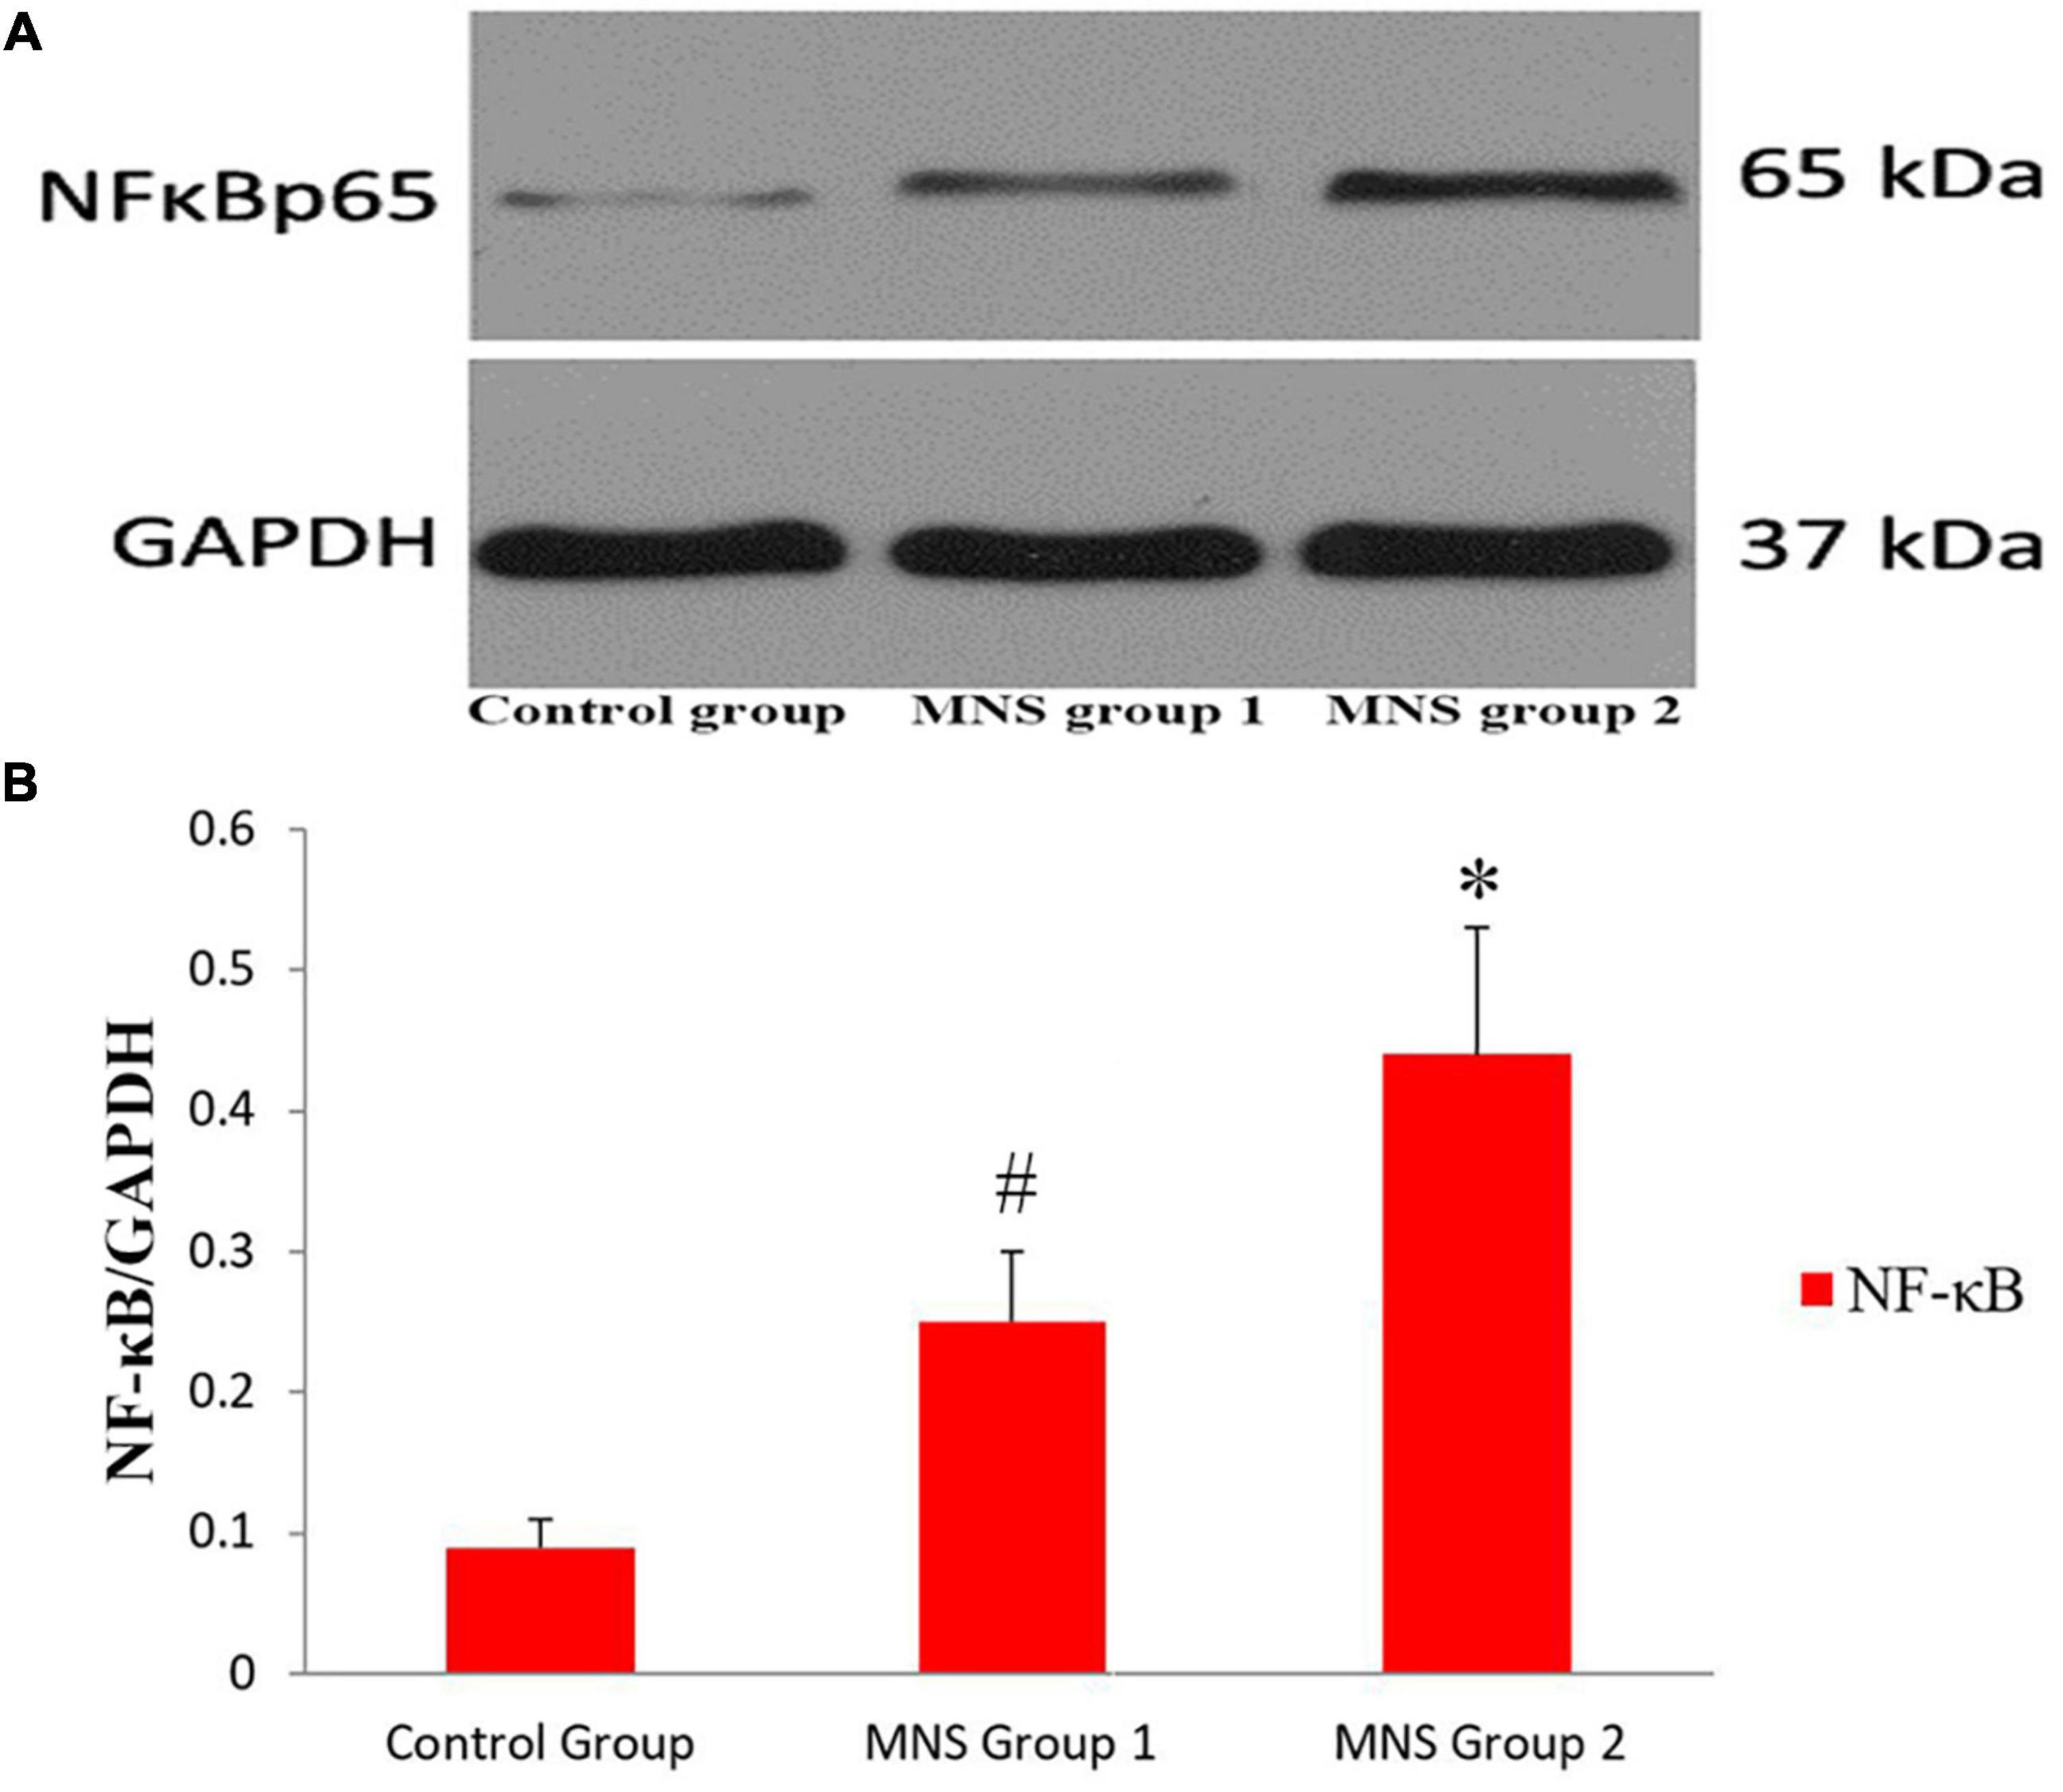

Western blot analysis

We compared Western blot results of ventricular tissues from the three groups (Figure 6). All immunoblot band intensity measurements were normalized to the intensity of the GADPH band in the loaded sample. Of note, the levels of NF-κB protein in the ventricular samples were significantly higher in the MNS group 2 than in the control group (0.44 ± 0.09 vs. 0.09 ± 0.02, P < 0.01) and in the MNS group 1 (0.44 ± 0.09 vs. 0.25 ± 0.05, P < 0.01). Compared to the control group, NF-κB protein expression was higher in the MNS group 1 (0.25 ± 0.05 vs. 0.09 ± 0.02, P < 0.01).

Figure 6. Expression of nuclear transcription factor-κB (NF-κB) protein in the left ventricular tissues. (A,B) Representative examples and quantitative analyses of NF-κB expression in the control, median nerve stimulation (MNS) group 1, and MNS group 2 dogs. #P < 0.01 vs. control group and MNS group 2; *P < 0.01 vs. control group.